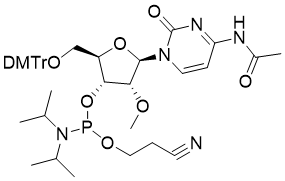

馬鞍山致研生物醫(yī)藥科技有限公司成立于馬鞍山市鄭浦港新區(qū)現(xiàn)代產(chǎn)業(yè)園。公司專(zhuān)注于生物小分子、醫(yī)藥中間體相關(guān)產(chǎn)品的研發(fā)和生產(chǎn),產(chǎn)品主要包括DNA亞磷酰胺單體、RNA亞磷酰胺單體、特殊單體以及按照客戶(hù)要求定制的RNA和DNA,并且公司提供定制合成等方面的研究服...

馬鞍山致研生物醫(yī)藥科技有限公司成立于馬鞍山市鄭浦港新區(qū)現(xiàn)代產(chǎn)業(yè)園。公司專(zhuān)注于生物小分子、醫(yī)藥中間體相關(guān)產(chǎn)品的研發(fā)和生產(chǎn),產(chǎn)品主要包括DNA亞磷酰胺單體、RNA亞磷酰胺單體、特殊單體以及按照客戶(hù)要求定制的RNA和DNA,并且公司提供定制合成等方面的研究服...